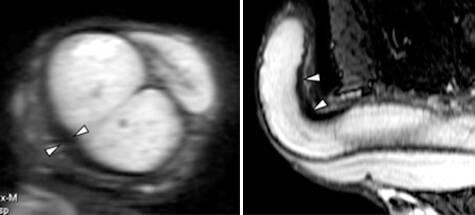

Для диагностики хронического кавернита используют уретроскопию и кавернозографию. Последнее исследование предусматриваем рентген пениса в состоянии эрекции. Перед этой процедурой вводят контрастное вещество. Серия полученных снимков позволяет выявить атрофированные фрагменты и бляшки, а также позволяет получить информацию о структуре кавернозных тел и др.